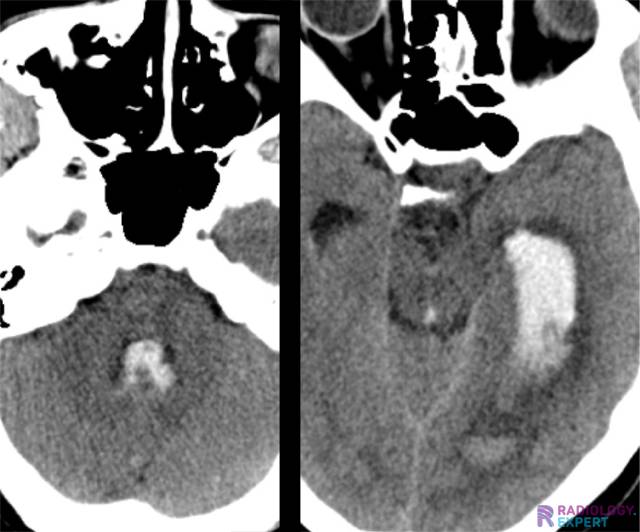

Extensive intraventricular blood in the left lateral ventricle, the aqueduct and the 4th ventricle. Extensive intraventricular blood in the left lateral ventricle, the aqueduct and the 4th ventricle.

Click image to see overlay